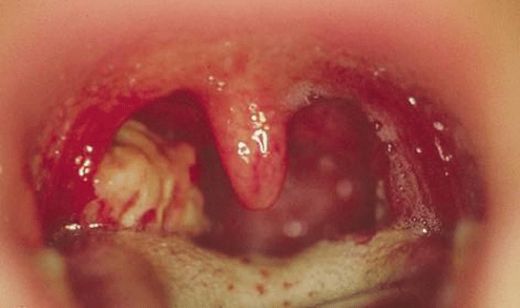

Bademcik şişmesi, tıpta "tonsillit" olarak adlandırılan bir durumu ifade eder ve bademciklerin iltihaplanmasıyla karakterizedir. Bu durum, çeşitli etkenler nedeniyle ortaya çıkabilir ve genellikle boğaz ağrısı, yutkunma güçlüğü, yüksek ateş gibi belirtilerle kendini gösterir. Bademcik şişmesi tedavisinde ilaç kullanımı önemli bir yer tutmaktadır. Bu makalede, bademcik şişmesi için ilaç kullanımının faydaları, türleri ve dikkat edilmesi gereken noktalar üzerinde durulacaktır. Bademcik Şişmesinin Nedenleri Bademcik şişmesinin birçok nedeni olabilir; bunlar arasında:

Bademcik Şişmesi Belirtileri

Bademcik şişmesi genellikle boğazda ağrı, yutkunmada zorluk, öksürük ve bazen ateş gibi belirtilerle kendini gösterir. Bu belirtiler, günlük yaşamı oldukça zorlaştırabilir ve rahatsız edici bir durum yaratabilir.

Eğer belirtiler şiddetliyse, birkaç gün içinde geçmiyorsa veya yüksek ateş, şiddetli boğaz ağrısı gibi ek belirtiler varsa, en kısa sürede doktora gitmek en uygun zaman olacaktır. Erken müdahale, olası komplikasyonları önleyebilir.